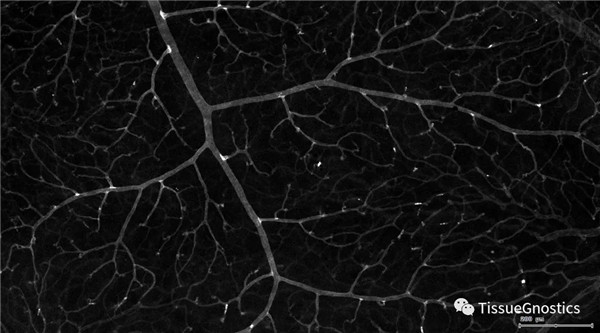

Ѫ¹Üʶ±ð£ºÆ¾¾ÝTexa RedͨµÀ½øÐÐʶ±ð£¬²¢È¥³ýÃæ»ýСµÄ¼°·Çͬһ½¹ÃæµÄѪ¹Ü£¬½ö¶ÔÈ·¶¨µÄÇåÎúµÄͬһ½¹ÃæµÄ´óѪ¹Ü½øÐÐÃæ»ýͳ¼Æ¡£

Ѫ¹ÜÓëС½ºÖÊϸ°ûµÄ¾àÀë

Ѫ¹ÜÓëС½ºÖÊϸ°ûµÄ¾àÀë0-0.1¦Ìm£¨ºìÉ«¿òÏß±ê¼Ç£©

Ѫ¹ÜÓëС½ºÖÊϸ°ûµÄ¾àÀë0.1-1¦Ìm£¨·ÛÉ«±ê¼Ç£©

Ѫ¹ÜÓëС½ºÖÊϸ°ûµÄ¾àÀë1-3¦Ìm£¨·ÛÉ«±ê¼Ç£©